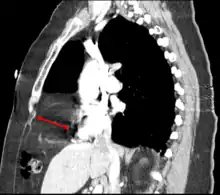

a)Posterolateral diaphragmatic hernia was discovered b) small bowel loops entering the thorax c) after reducing contents d)extreme left lung hypoplasia -